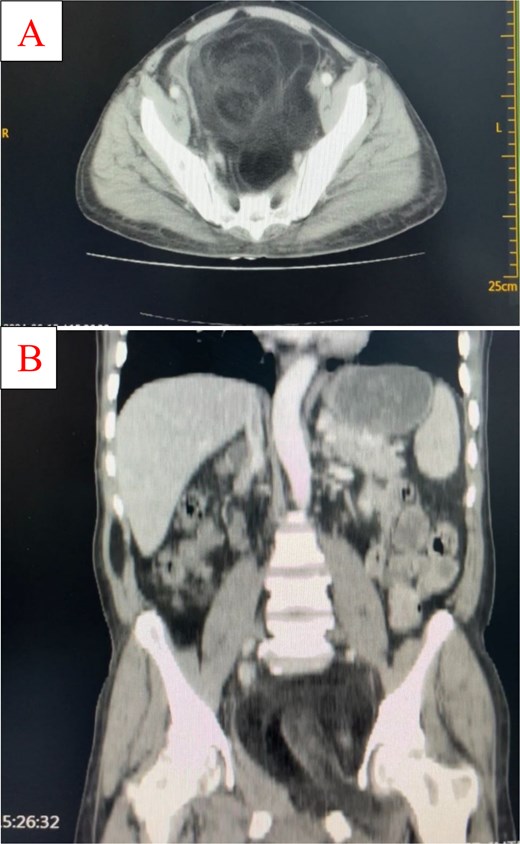

Ultrasonography revealed a well-differentiated retroperitoneal mass measuring approximately 14 × 12 × 21 cm. The chest radiography and electrocardiography findings were normal. CT scan showed huge pelvi-abdominal fatty mass exhibiting central soft tissue component measuring 15.5 × 12.3 × 22.8 cm in the greatest anterioposterior, transverse, and coroncodal dimensions, respectively, and a mean density of −83 HU. The mass was well-defined; it is abutting the left pelvis side wall exiting (herniating) through the left obturator and the right greater sciatic foramina into the left groin and right buttock. The mass is compressing and displacing the bladder anteriorly and to the right side and the rectum and sigmoid to the right side against the pelvis side wall. The line of cleavage is preserved; no aggressive behavior or bone destruction (Fig. 2).

Coronal (A) and sagittal (B) CT images demonstrating a large retroperitoneal fatty mass with central soft tissue density. The mass extends through the left obturator and right greater sciatic foramina, displacing the bladder anteriorly and pelvic organs laterally.